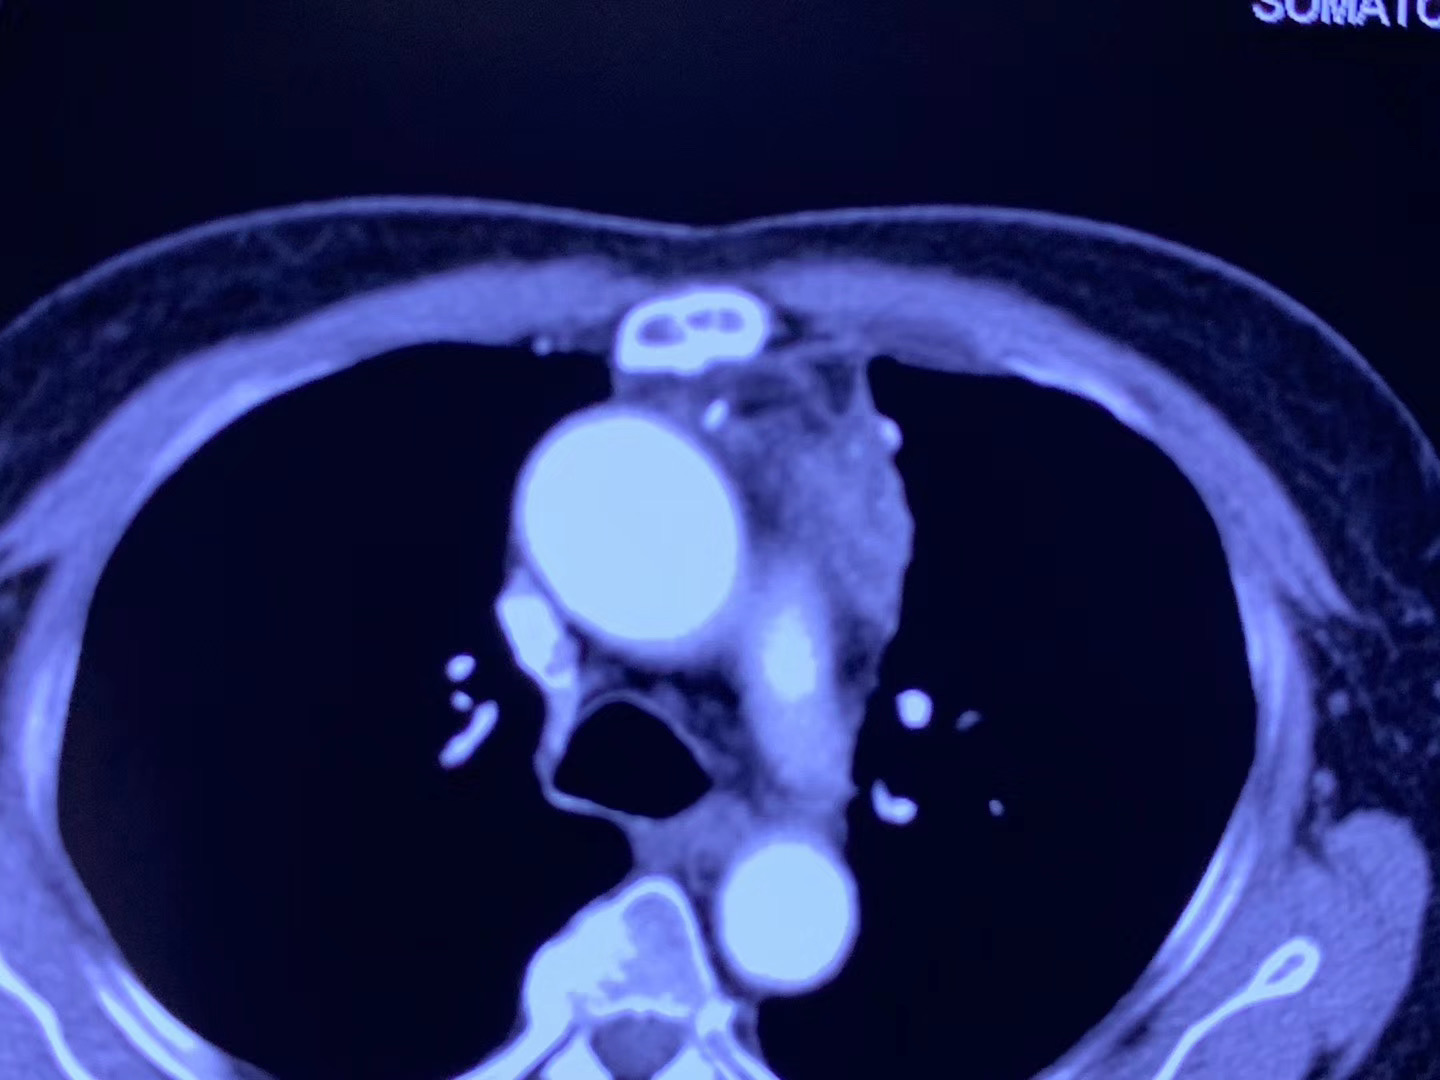

一位来自印尼患者,冠脉搭桥手术后患胸腺癌不适宜再手术,半年前已在我院行冷冻消融治疗,效果非常好。这次复查还有少许肿瘤残留,再次行冷冻消融治疗。

对不适宜手术的胸腺肿瘤,冷冻消融是一个非常好的选择。目前国际上发表的相关临床论文有四篇,分别是美国(25例)、日本(个案)、中国台湾(个案)、及中国!至今我院已经完成50多例的胸腺肿瘤冷冻消融,是国际上经验最多的医院之一。